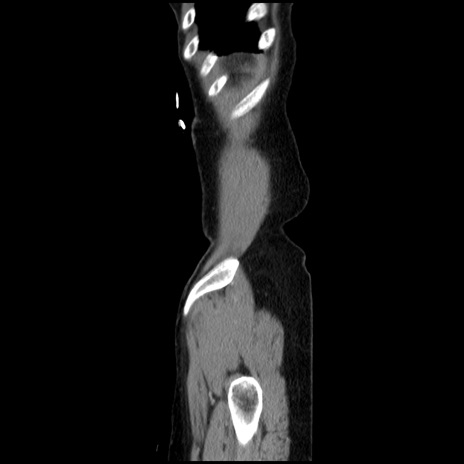

症例32(矢状断像)

【症例】40歳代 女性

【主訴】上腹部痛、嘔気・嘔吐

【現病歴】約9時間前頃から急に上腹部痛、嘔気、嘔吐が出現。改善しないため救急要請。

【既往歴】子宮頚癌(広汎子宮全摘術、放射線療法)、腸閉塞

【身体所見】腹部:平坦、軟、腸雑音亢進、上腹部を中心に腹部全体に圧痛あり。

【データ】WBC 8400、CRP 0.03